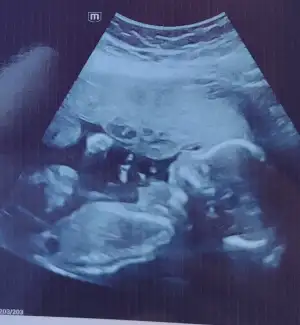

İyi aksamlar kızlar bugun doktor kontrolum vardi 1 aydir görmüyordum kızımı nasıl büyümüş hicbir sorun yok sukur gelisimide gayet guzel dedi 350 gr boyuda 24 cm olmuş 🥰 detayli ultrason için universite hastanesinde docent doktor var ondan zor bela randevu bulduk 23. Haftaya doktorum guzel bir hafta sorun olmaz dedi kasımın 4 unde detayli randevum var şeker yuklemesi icin henuz birsey demedi bende soracaktim unutmusum🫣yarinda saglik ocagina gidecegim tetanoz asisi icin 5 yil once oglumda asi oldugum icin bogmacali karma aşı varmis tek doz o yapilacak. Kizimin fotografini biraktim size nasil hatlari belli olmus ya yüzünü döndü birde agzi burnu gözü kafayi yedim 20+0 suan 🤭🤭

• IMG_20251014_224346.webp

IMG_20251014_224346.webp

48,4 KB · Görüntüleme: 54